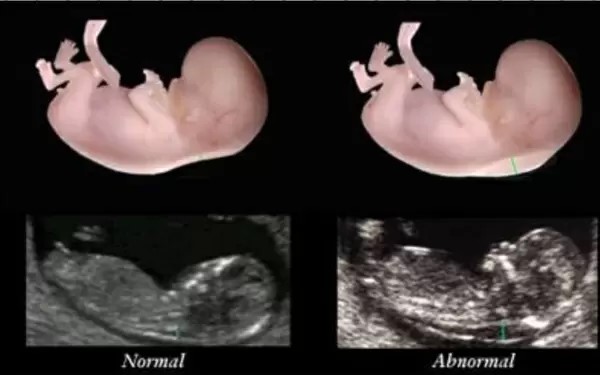

Siêu âm đo độ mờ da gáy thường được thực hiện vào tuần thứ 12 của thai kỳ để xác định chỉ số độ mờ da gáy có bình thường hay không. Nếu phát hiện ra dấu hiệu bất thường, bác sĩ có thể sẽ chỉ định thêm các xét nghiệm khác như NIPT, chọc ối… để cho kết quả chẩn đoán chính xác hơn.

Đối với trẻ phát triển bình thường, chỉ số độ mờ da gáy thường dưới 3.5. Vì vậy, độ mờ da gáy 1.5 ở tuần 12 được cho là chỉ số bình thường và các mẹ bầu không cần quá lo lắng.

– Ở tuần 12 thai kỳ, độ mờ da gáy tối đa là 2.5mm là chuẩn nên độ mờ da gáy 1.5 là bình thường.